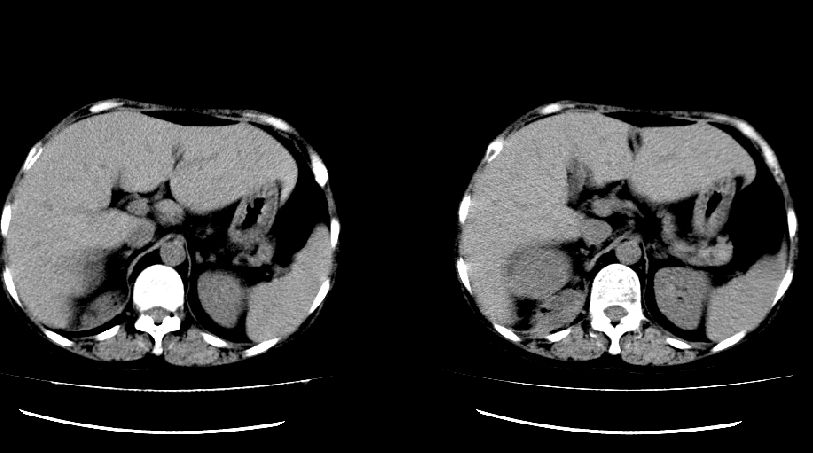

以下是引用liuyue在2008-7-19 10:17:00的发言:[br]考虑:1.肾周脓肿,肾实质、腰大肌及侧腹壁均受累及。 2.右肾囊肿。[br]建议:强化扫描,除外肾癌之可能。[br]

以下是引用zhengfaming在2008-7-19 14:48:00的发言:[br]右肾脓肿并感染可能性大,建议增强

以下是引用江广1996在2008-7-19 10:48:00的发言:[br]先考虑右侧肾周感染脓肿形成并累及腰大肌,右肾前侧有病灶考虑囊肿。